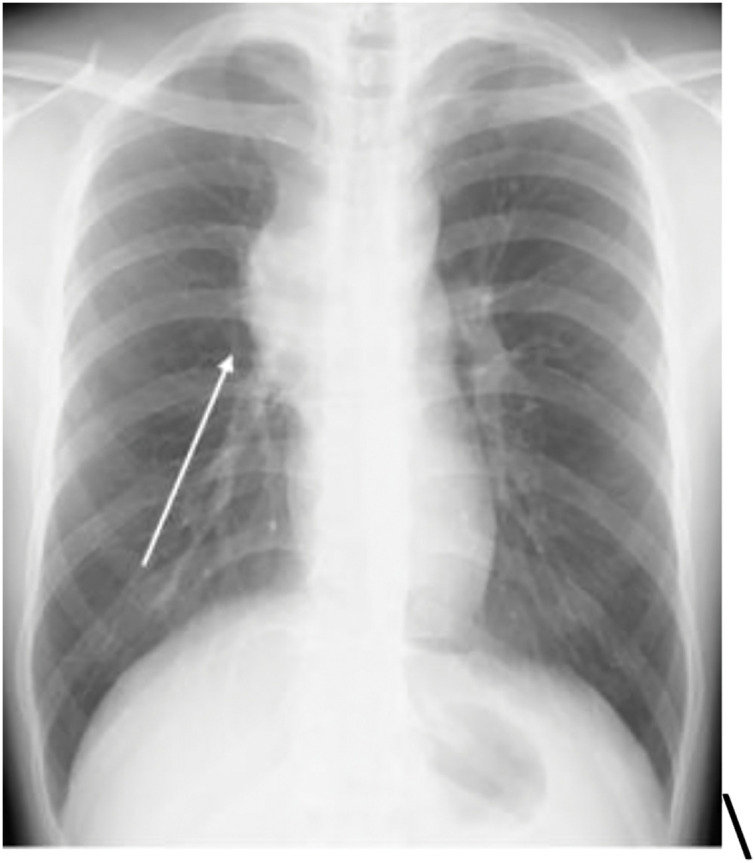

Case presentation: The patient was a 25-year-old man who had been experiencing labored breathing when leaning forward for the past month. Physical examination revealed distended jugular veins and neck edema. Chest computed tomography revealed an irregular mass measuring 80 mm in the anterior mediastinum, suggesting invasion of the superior vena cava. Additionally, fluorodeoxyglucose-positron emission tomography showed high accumulation in the same area, with a maximum standardized uptake value of 11.3. A tumor biopsy was performed under thoracoscopic guidance for definitive diagnosis. Histopathological examination of the resected specimen revealed a seminoma with granulomatous changes. Based on these findings, a diagnosis of anterior mediastinal seminoma with superior vena cava syndrome was made. It was classified as having a good prognosis, and the patient received three courses of induction chemotherapy with etoposide, cisplatin, and ifosfamide. Complete remission was achieved. Since then, the patient has been monitored every 3 months, with no recurrence or metastasis observed for approximately 2 years.